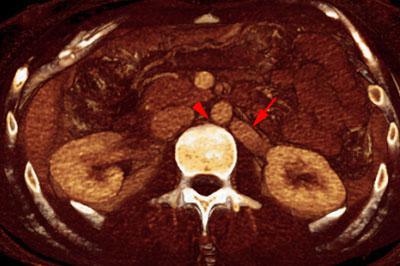

Síndrome del cascanueces retroaórtico

VR seccional. Visión axial caudal. TC abdominal contrastado en fase venosa que muestra una discreta dilatación de la vena renal izquierda (flecha). Existe una disminución del espacio entre aorta abdominal y cuerpo vertebral (punta de flecha)